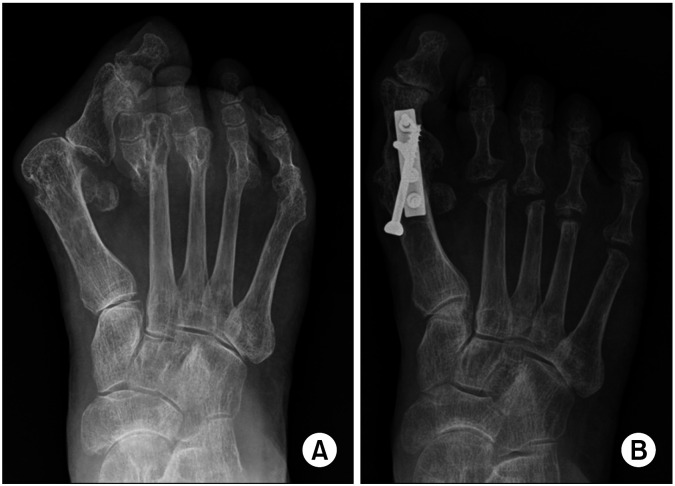

Objective: To study the clinical and radiologic factors related with overall patient satisfaction of joint scarifying reconstruction on severe rheumatoid forefoot deformity (RFD).

Methods: Forty cases of RFD were retrospectively enrolled. A questionnaire on the factors for patient's expectations and satisfactions of the greater and lesser toes was administered, including repression of relapse in deformity (D), pain reduction (P), improvement in shoe wearing (S), barefoot activity (B), and appearance (A). Overall satisfaction were assessed using the 5-digit-scale. Hallux valgus angle, 1, 2 intermetatarsal angle, and other radiologic parameters were measured. Pearson's correlation and multiple linear regression analyses were used to evaluate the relationships between these factors and overall satisfaction.

Results: Overall satisfaction was 4.0±0.82. Postoperative radiologic parameters were corrected in adequate range. Visual analog scale (VAS) was reduced from 7.2±2.1 to 2.2±1.8. For the greater toe, patient's expectations (D, P, S, B, and A) were 4.2, 4.1, 3.0, 2.5, 2.7 and satisfactions were 4.2, 4.0, 3.4, 3.5, 3.3, respectively. For the lesser toes, patient's expectations (D, P, S, B, and A) were 3.9, 4.1, 3.4, 3.0, 2.8, and satisfactions were 3.4, 4.0, 3.4, 3.6, 2.9, respectively. Satisfactions with P and B, and reduction amounts of VAS were significantly correlated with overall satisfaction.

Conclusion: Although forefoot reconstruction with a joint sacrificing procedure is non-physiological, it could be a good surgical option for severe RFD. Each patient's expectations and satisfactions with this procedure could vary. Thus, it seems important to inform patients preoperatively that expectation could be fulfilled well or less.